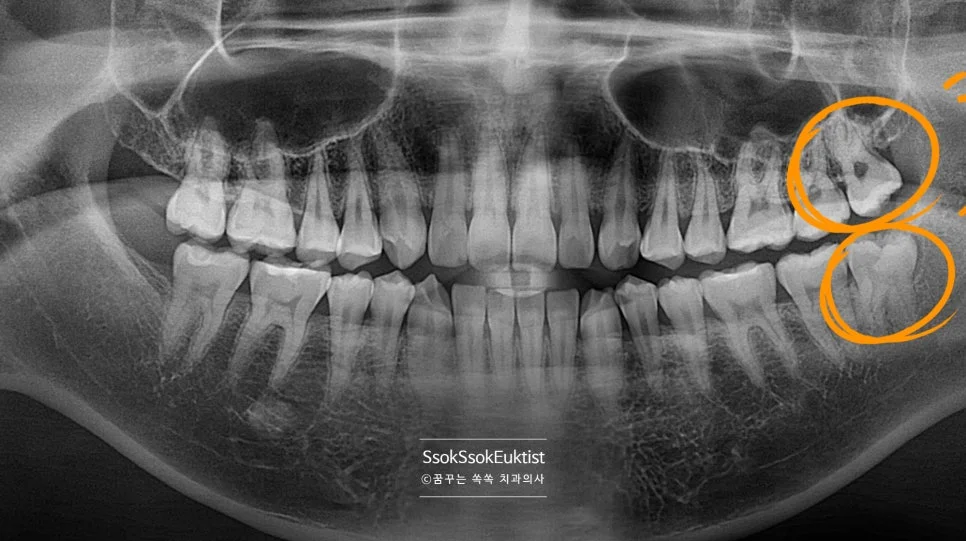

파노라마 엑스레이 — 상악과 하악 사랑니 위치 전체 확인

충치가 심하게 생긴 왼쪽 위아래 사랑니

충치가 심하게 생겨 사랑니 통증으로 오신 분인데요, 왼쪽 위아래 사랑니입니다.

바로 앞 치아는 멀쩡한데 왜 유독 사랑니만 충치가 있는 걸까요?

사랑니가 서로 닿아 기능하지 않기 때문입니다!

어금니의 씹는 과정(저작)은 어금니 머리를 세척, 청소하는 효과도 있는데요. 어금니가 서로 닿지 않으면 치아의 머리 면에 음식물이 계속 고여있으면서 충치가 생기게 됩니다!

예쁘게 1분 안에 발치하면 됩니다!